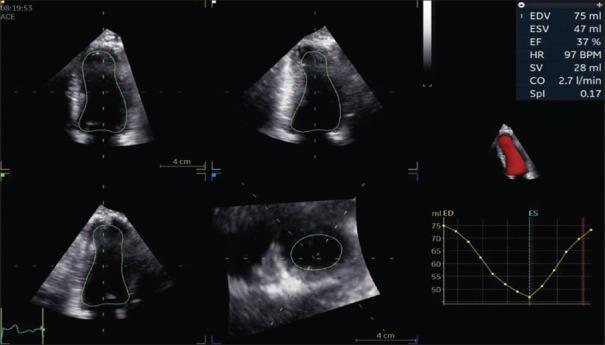

Idiopathic hypereosinophilic syndrome (HES) is a rare disorder characterized by persistent hypereosinophilia leading to multi-organ dysfunction. Its clinical manifestations vary widely; however, cardiac and neurological involvement are the leading causes of morbidity and mortality. Corticosteroids are the initial treatment of choice, but in idiopathic HES resistant to corticosteroids, second-line therapy should be considered. Imatinib is usually reserved for patients with a positive platelet-derived growth factor receptor A (PDGFR-A) mutation; however, its use in idiopathic HES with a negative PDGFR mutation is debatable given that such patients usually respond well to high doses of corticosteroids. Here, we present a case of a young male with corticosteroid-refractory idiopathic HES successfully treated with imatinib. The patient presented with features suggestive of acute coronary syndrome and confusion. A coronary angiogram was normal. Echocardiography showed an ejection fraction of 37%, and brain imaging showed evidence of multifocal cerebral thromboembolic infarcts. During the hospital stay, the patient developed diffuse alveolar hemorrhage. Biochemically, it was noted that the patient had hypereosinophilia. Through thorough workup, a diagnosis of idiopathic HES was established. The patient was started on high-dose corticosteroid (500 mg intravenous methylprednisolone daily) followed by a maintenance dose of prednisolone (0.5 mg/kg/day), but had no response. Second-line therapy with imatinib (400 mg per oral daily for 4 days and then down-titrated to 100 mg daily) was initiated, which resulted in drastic biochemical and clinical improvements. This case report supports the efficacy of imatinib as a second-line agent in corticosteroid-resistant idiopathic HES with a negative PDGFR mutation.

特发性嗜酸性粒细胞增多综合征(HES)是一种罕见疾病,其特征为持续性嗜酸性粒细胞增多并导致多器官功能障碍。其临床表现差异很大;然而,心脏和神经系统受累是发病和死亡的主要原因。皮质类固醇是初始治疗的首选药物,但对于对皮质类固醇耐药的特发性HES,应考虑二线治疗。伊马替尼通常用于血小板衍生生长因子受体A(PDGFR-A)突变阳性的患者;然而,鉴于此类患者通常对高剂量皮质类固醇反应良好,其在PDGFR突变阴性的特发性HES中的应用存在争议。在此,我们报告一例年轻男性皮质类固醇难治性特发性HES患者,经伊马替尼成功治疗。该患者表现出提示急性冠状动脉综合征和意识模糊的症状。冠状动脉造影正常。超声心动图显示射血分数为37%,脑部影像学显示有多灶性脑血栓栓塞性梗死的证据。住院期间,患者出现弥漫性肺泡出血。生化检查发现患者有嗜酸性粒细胞增多。通过全面检查,确诊为特发性HES。患者开始接受高剂量皮质类固醇治疗(每日静脉注射500 mg甲泼尼龙),随后给予泼尼松龙维持剂量(0.5 mg/kg/天),但无反应。启动伊马替尼二线治疗(每日口服400 mg,共4天,然后减至每日100 mg),这导致了生化和临床方面的显著改善。本病例报告支持伊马替尼作为二线药物在PDGFR突变阴性的皮质类固醇耐药性特发性HES中的疗效。